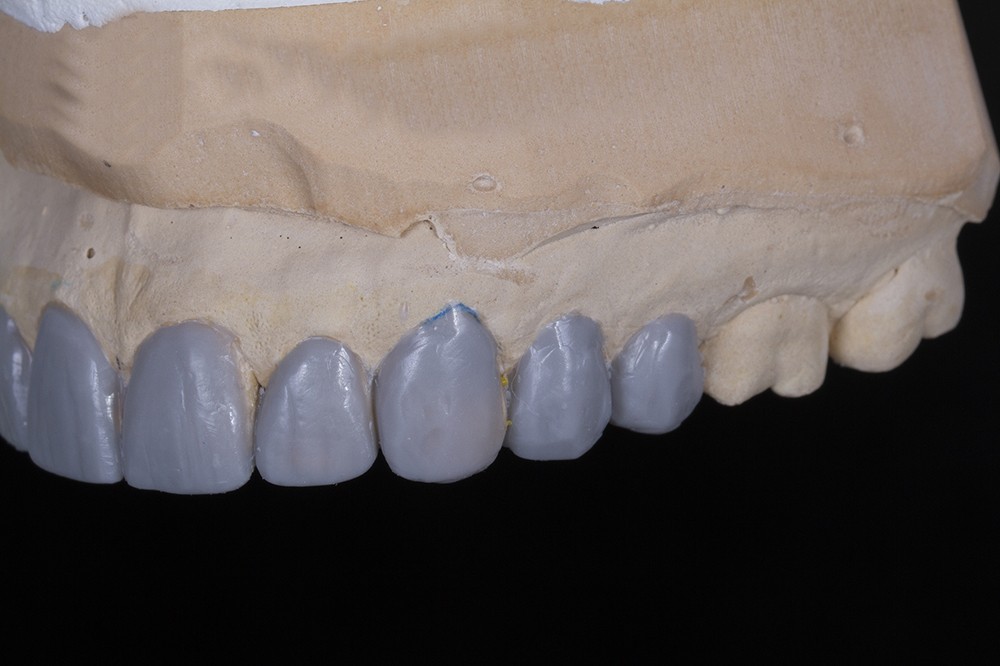

Le wax-up est préférentiellement élaboré en deux temps [17] : un wax-up dit esthétique, concernant uniquement les faces vestibulaires des dents de 15 à 25 puis un wax-up complet.

La première étape est facilitée par l’élaboration d’un smile design préalable, associé aux photographies extra/intra-buccales. Le prothésiste aura de ce fait une base de travail lui permettant de gérer l’allongement des bords libres d’un point de vue esthétique [18].

En clinique, le mock-up est ensuite réalisé en résine bis-acryl pour valider ce projet esthétique. Si nécessaire, des corrections peuvent y être apportées et retransmises, le cas échéant, au laboratoire [19].